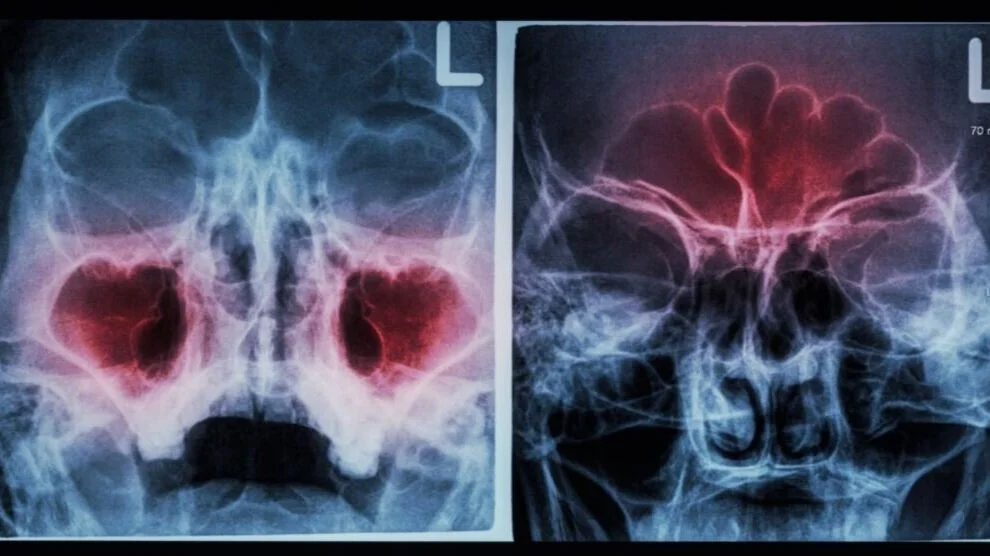

CT SCANNER

A CT scan is a piece of medical equipment that uses a series of X-ray images to create two and three-dimensional views of the internal anatomy. A CT scan of the sinuses may be suggested by your provider to better detail possible diseases involving your sinuses or nasal cavity that may be the cause of your symptoms.

Radiation doses from our CT scanner are 10 times less than CT scans from the hospital. Furthermore, unlike hospital-based CT scanners, our in-office scanner is upright. This provides our patient who may have mobility issues, chronic back pain, shortness of breath or other discomforts when laying flat a more comfortable experience.

Imaging is sometimes covered by your office copay, making it a more affordable option. Thus, having your sinuses scanned in our office is not only convenient and efficient, but overall safer for our patients with reduced radiation exposure.